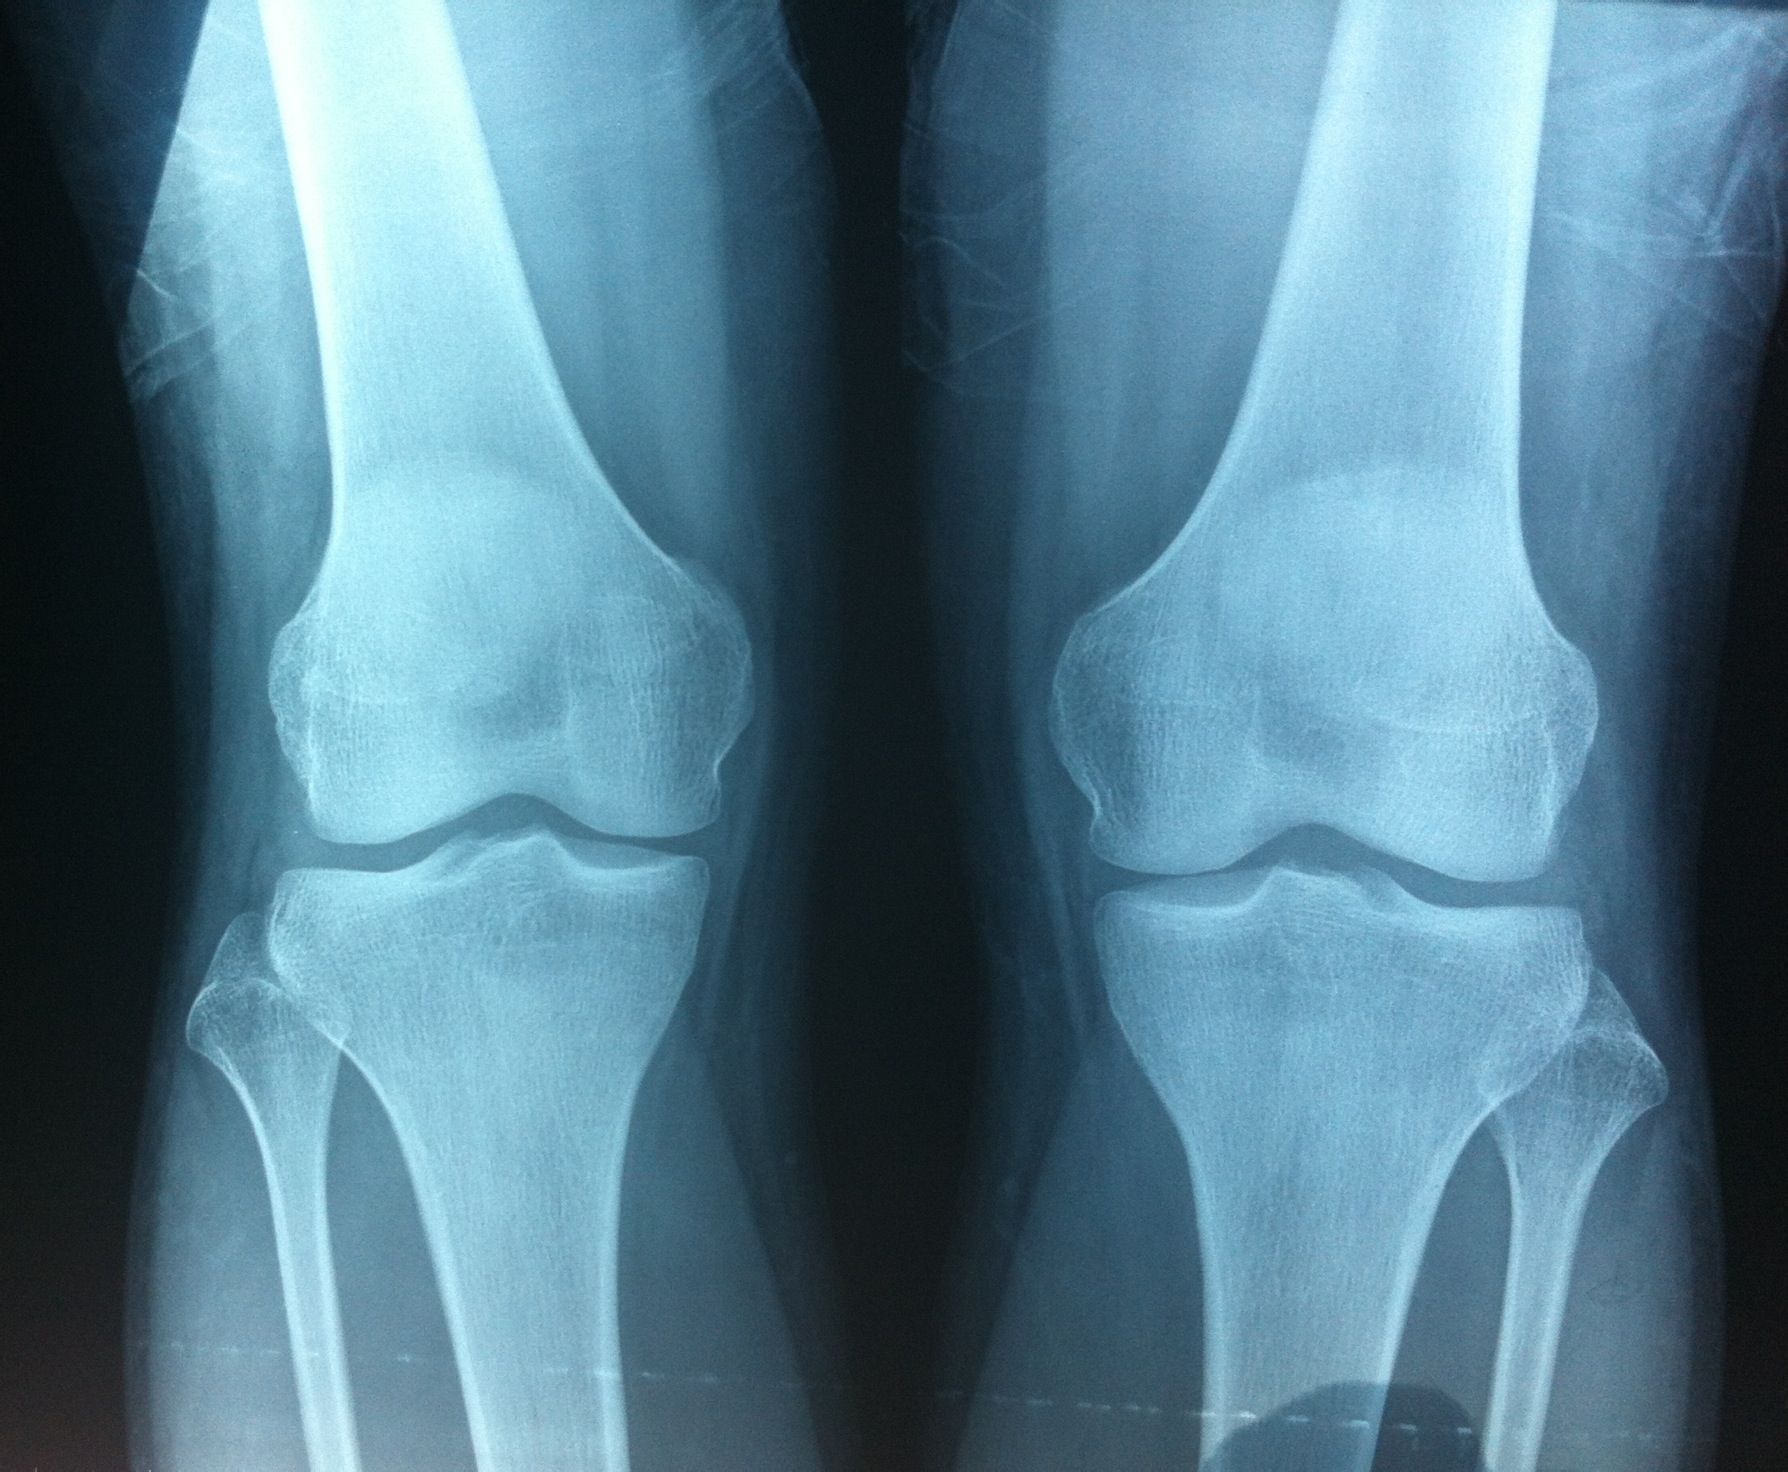

骨骺与骨龄的关系

在未成年之前,骨两侧连接处为骺软骨,骺软骨在少年时期增生,骨化.

成年后骺软骨骨化,原骺软骨处形成一线状痕迹,称为骺线.